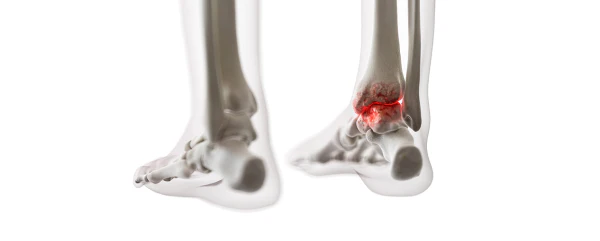

1) 한 군데 관절(엄지발가락, 발목, 무릎 등)이 갑자기 붓고 빨갛게 변하며, 손을 움켜쥘 수 없을 정도로 심한 통증이 발생합니다.

4) 엄지발가락 관절에 염증이 잘 발생하는 것이 특징이며, 무릎, 발, 발목, 손목, 팔꿈치 등 다른 관절에서도 발생할 수 있습니다.